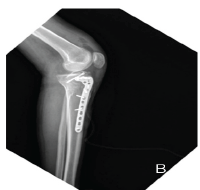

Stage 1 surgery was done via a posterior approach through the previous scar. Intraoperatively, after opening the fascia lata, we noticed a large soft tissue mass around the trochanter and acetabular region which was dark reddish brown in color. There was severe osteolysis around the acetabulum and trochanteric region. After the excision of the soft tissue mass, the material was sent for histopathology and culture (Fig. 5b). The acetabular component was completely loose, so it was removed along with the ceramic liner (Fig. 5a). There was no damage seen on the ceramic femoral head and acetabular liner. The trunnion of the femoral stem was normal. Since the femoral stem was well integrated, extended trochanteric osteotomy was done to remove the femoral stem. Extended trochanteric osteotomy was closed with encircling wiring and plating (Fig. 6). His histopathology reports showed fibrin, proliferating fibroblasts, hemosiderin-laden macrophages, lymphocytes, and chronic granulation tissue findings suggestive of pseudotumor formation. There was no evidence of malignancy (Fig. 7).